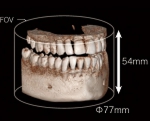

当院では、3D撮影ができる歯科用CTを導入しています。

従来のレントゲンは2次元の平面図でしたが、歯科用CTでは、3次元で細部まで鮮明に映し出すことができるので、より正確な診断が可能となりました。